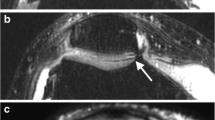

On WE 3D FLASH MR imaging normal cartilage appeared with high signal and good contrast to synovial fluid and other surrounding structures, especially subchondral bone (Fig. 1). Thirty true-positive, 34 false-negative (6 grade 1a, 4 grade 1b, 4 grade 2a, 13 grade 2b, 6 grade 3a, 1 grade 3b), 85 true-negative, and seven false-positive findings resulted in a sensitivity, specificity, positive and negative predictive value, and accuracy of 46%, 92%, 81%, 71%, and 74%, respectively. Significant correlations between WE 3D FLASH and arthroscopy for lesion grading were found on the patella and femoral trochlea and for lesion sizing on the femoral trochlea (Tables 2, 3).

On FS PDw TSE MR imaging, intact cartilage appeared with low to intermediate signal (Fig. 1). High signal intensity of joint fluid and cartilage edema assisted in the visualization of cartilage contour irregularities and internal derangement (Fig. 2, 3, 4). Fifty-eight findings were true-positive, six false-negative (3 grade 1a, 1 grade 1b, 1 grade 2a, 1 grade 2b), two false-positive, and 90 true-negative (Table 1). Sensitivity, specificity, positive predictive value, negative predictive value, and accuracy were 91%, 98%, 96%, 94%, and 95%, respectively. The correlation between arthroscopy and FS PDw TSE for grading and sizing cartilage lesions was significant in all compartments (Tables 2, 3).

A 54-year-old woman with an arthroscopically proven grade 1b lesion of the lateral patellar facet in the transverse plane. No distinct signal alterations or surface irregularities are visible with WE 3D FLASH (A) MR imaging. Note the area of increased internal cartilage signal (arrow) on FS PDw TSE (B). A WE 3D FLASH: 28/11 ms, flip angle 40°. B FS PDw TSE: 3433/15 ms, flip angle 180°